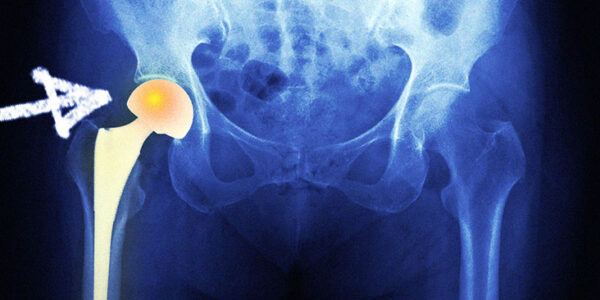

Hemiartroplastia bipolar: descripción general y qué esperar

La hemiartroplastia bipolar (BHA) es un tratamiento quirúrgico para las fracturas del cuello femoral de la cadera. Una articulación artificial con dos cojinetes reemplaza la articulación dañada. Los cojinetes permiten que la cabeza gire durante el movimiento, evitando el desgaste…